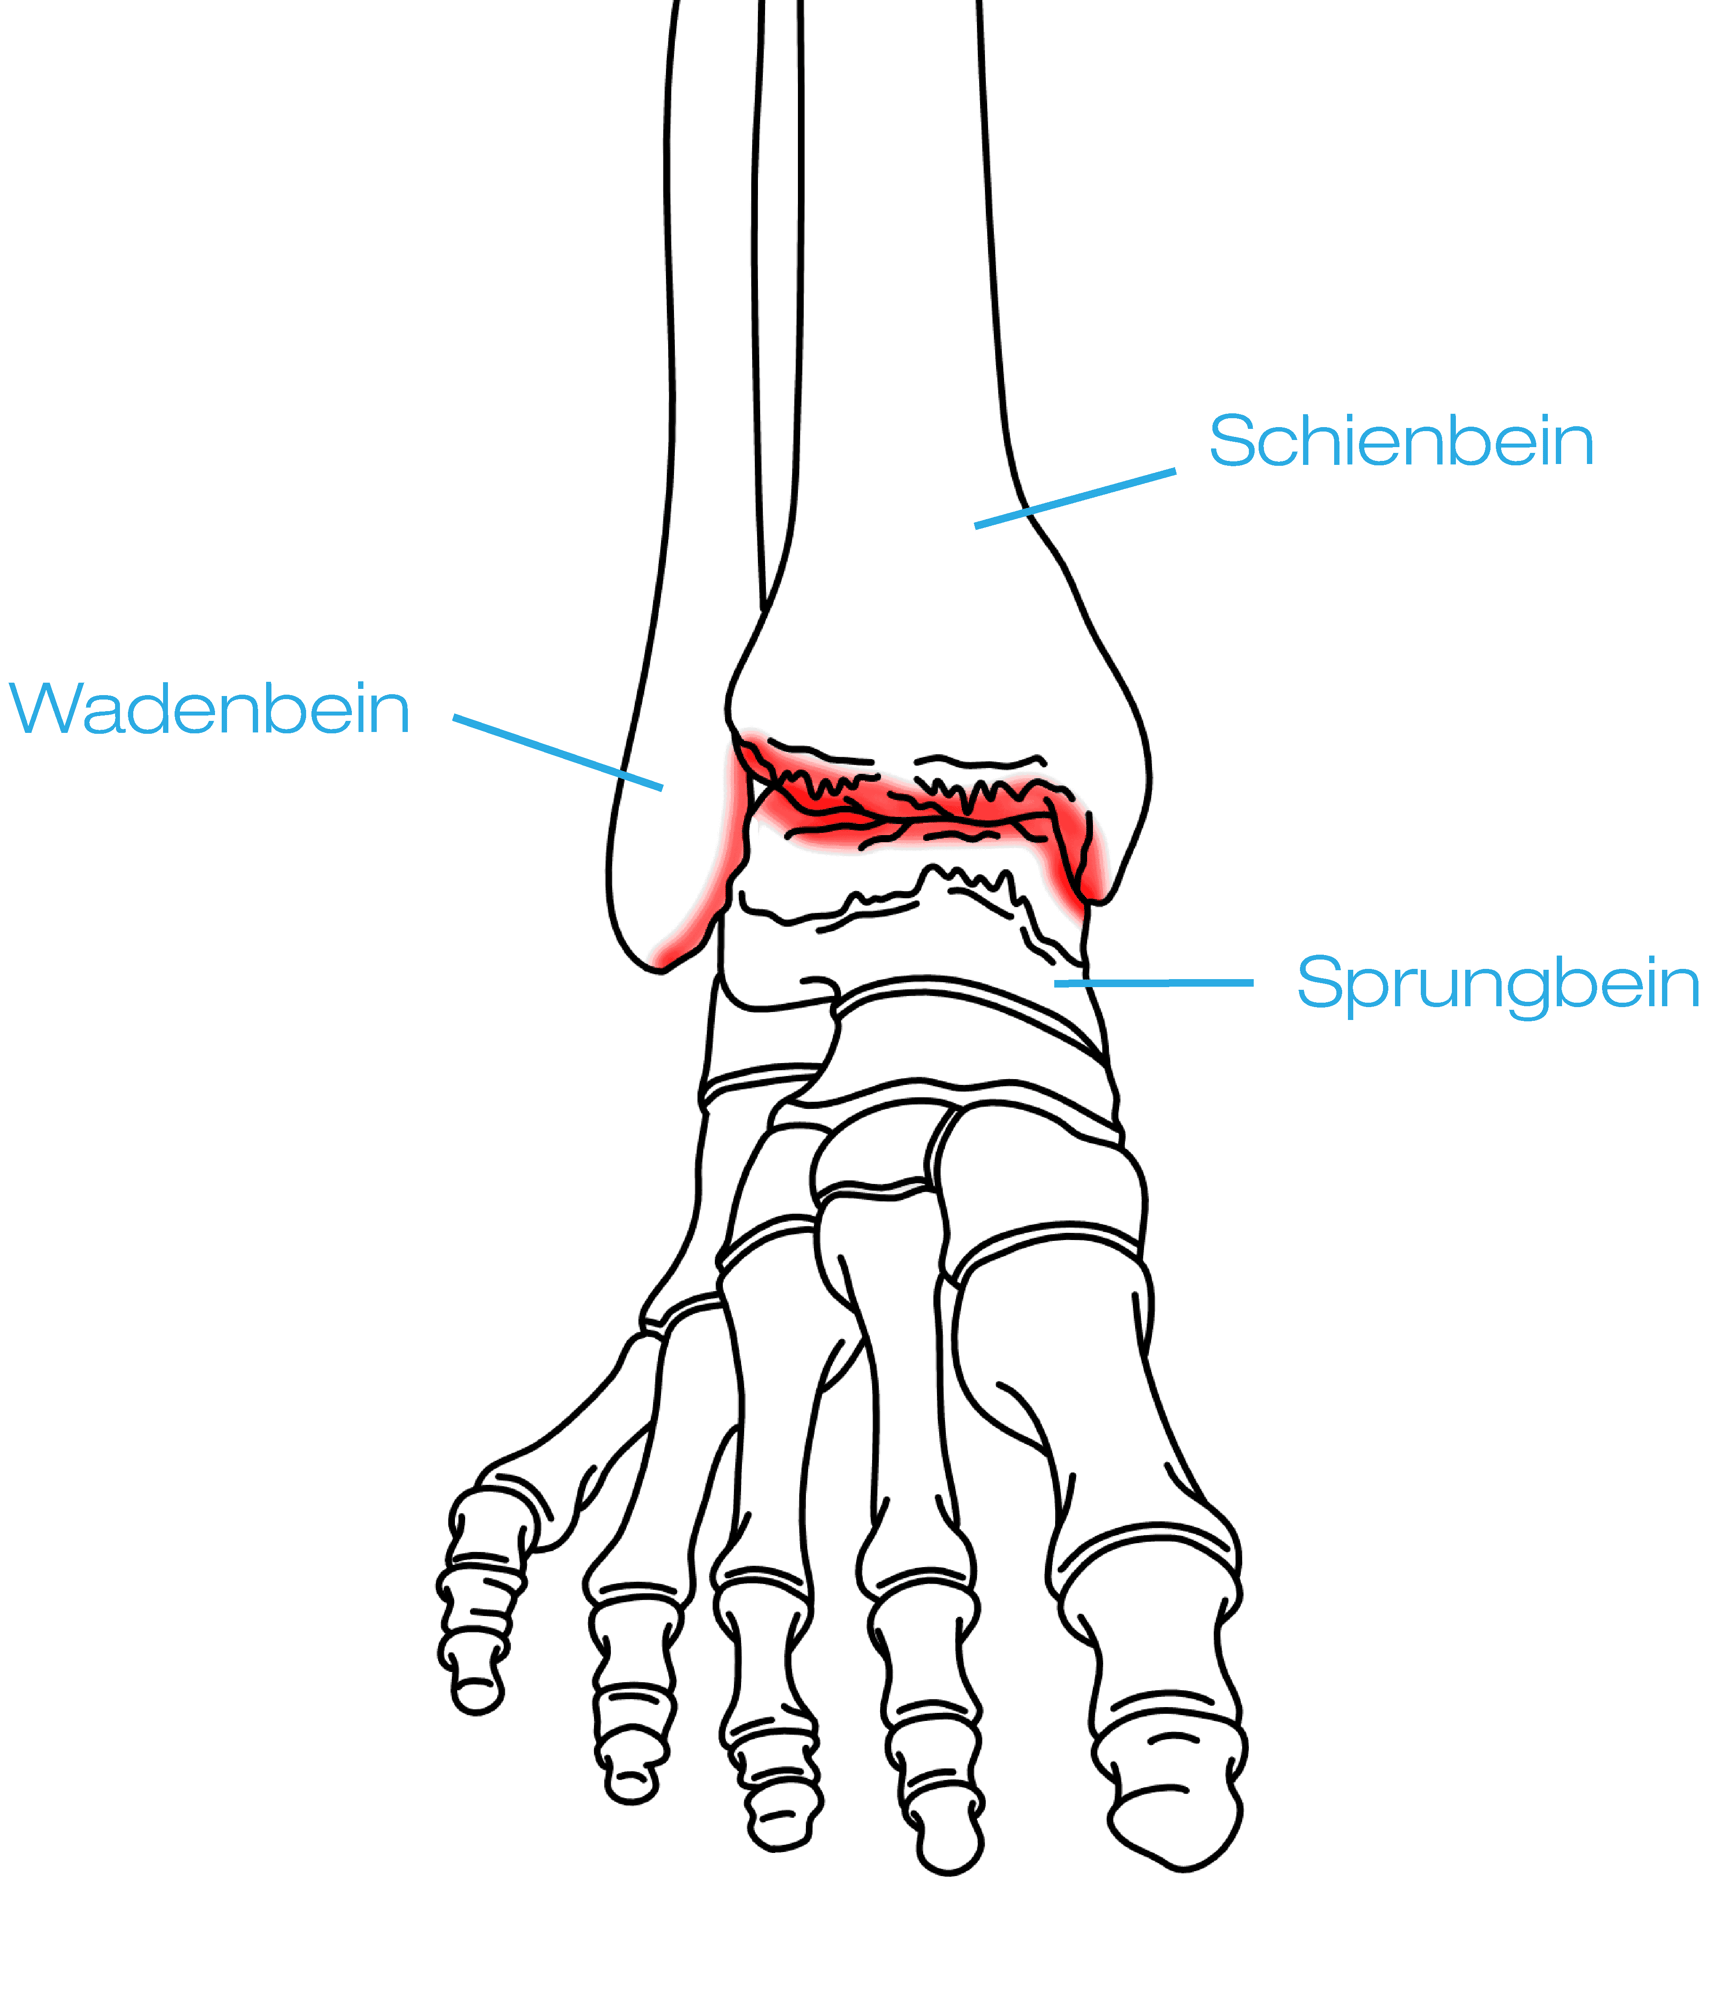

Grundlegend kann bei der Ursache der Arthrose im Sprunggelenk zwischen primärer und sekundärer Sprunggelenksarthrose unterschieden werden. „Die Ursache von sekundärer Arthrose im Sprunggelenk ist in vielen Fällen ein verjährter Bruch im Sprunggelenk. Man spricht hier auch von einer posttraumatischen Arthrose“, so der Arthrose Experte Prim. Dr. Norbert Freund. Sprunggelenksarthrose kann aber auch durch Fehlbelastungen und unbehandelte Fehlstellungen auftreten. In solchen Fällen spricht man von einer primären Sprunggelenksarthrose. Solche Fehlstellungen können zum Beispiel Plattfüße oder auch O oder X-Beine sein. Deutlich häufiger als das Sprunggelenk, sind Hüfte sowie Knie von Arthrose betroffen.

Arthrose im Sprunggelenk